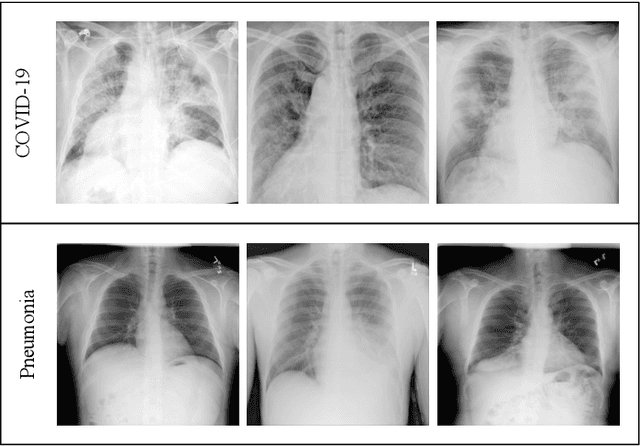

Deep Learning for Screening COVID-19 using Chest X-Ray Images

Figure 1 for Deep Learning for Screening COVID-19 using Chest X-Ray Images

Figure 2 for Deep Learning for Screening COVID-19 using Chest X-Ray Images